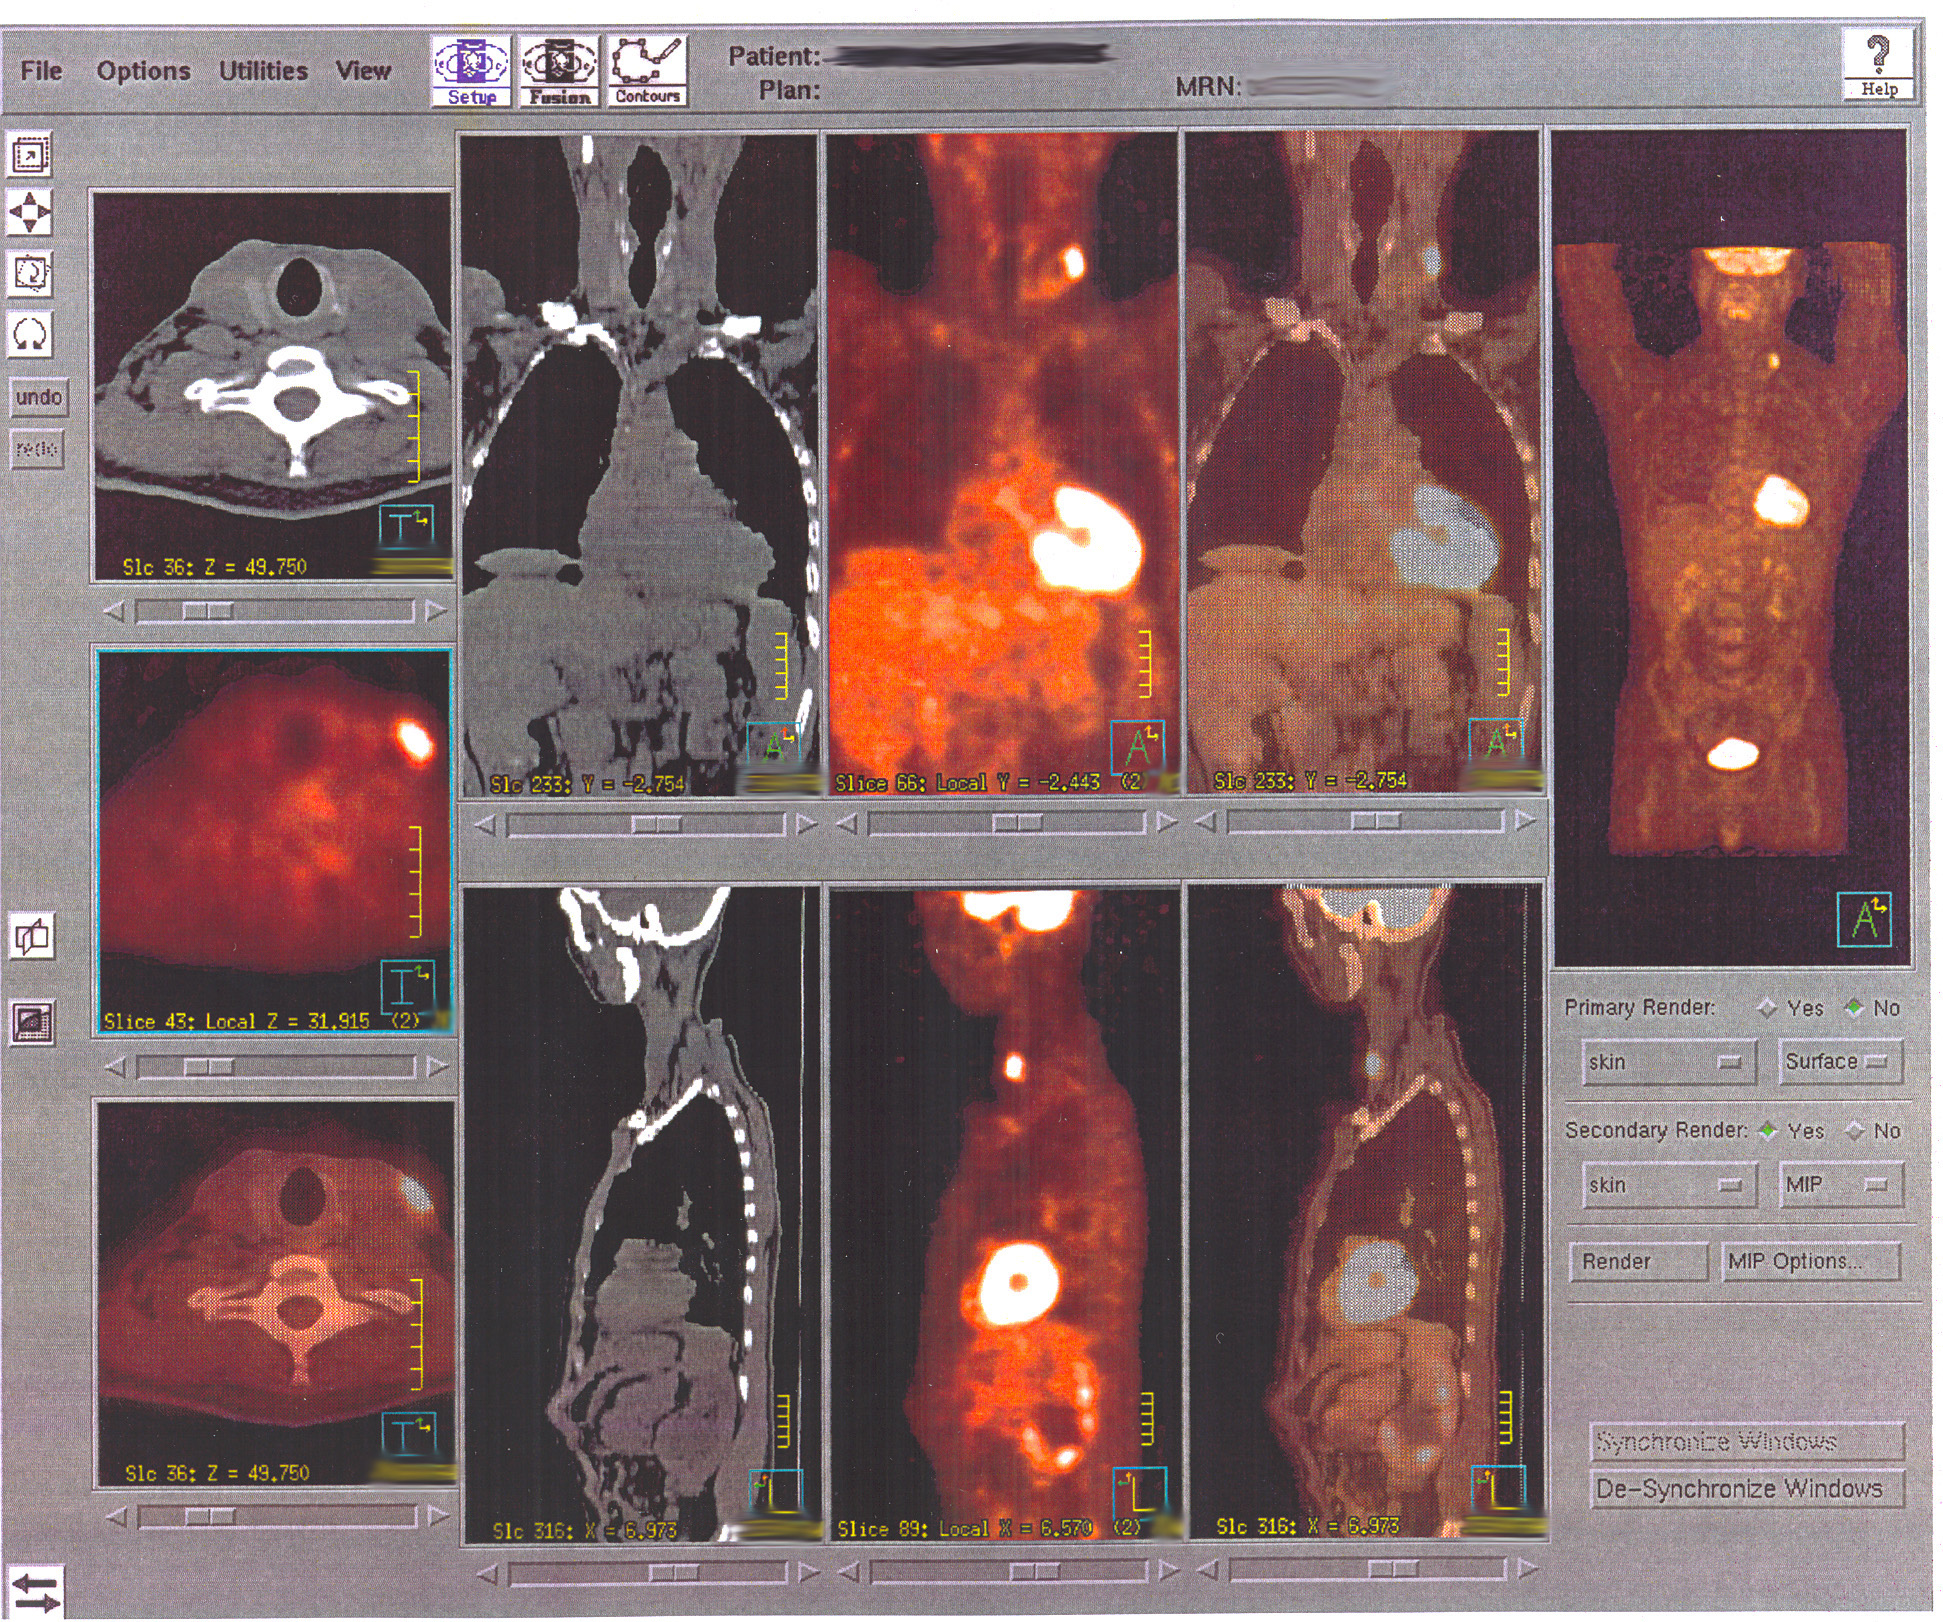

Whole-body PET/CT phantom with FDG-avid lesions in lung, liver, and lymph nodes for oncologic staging